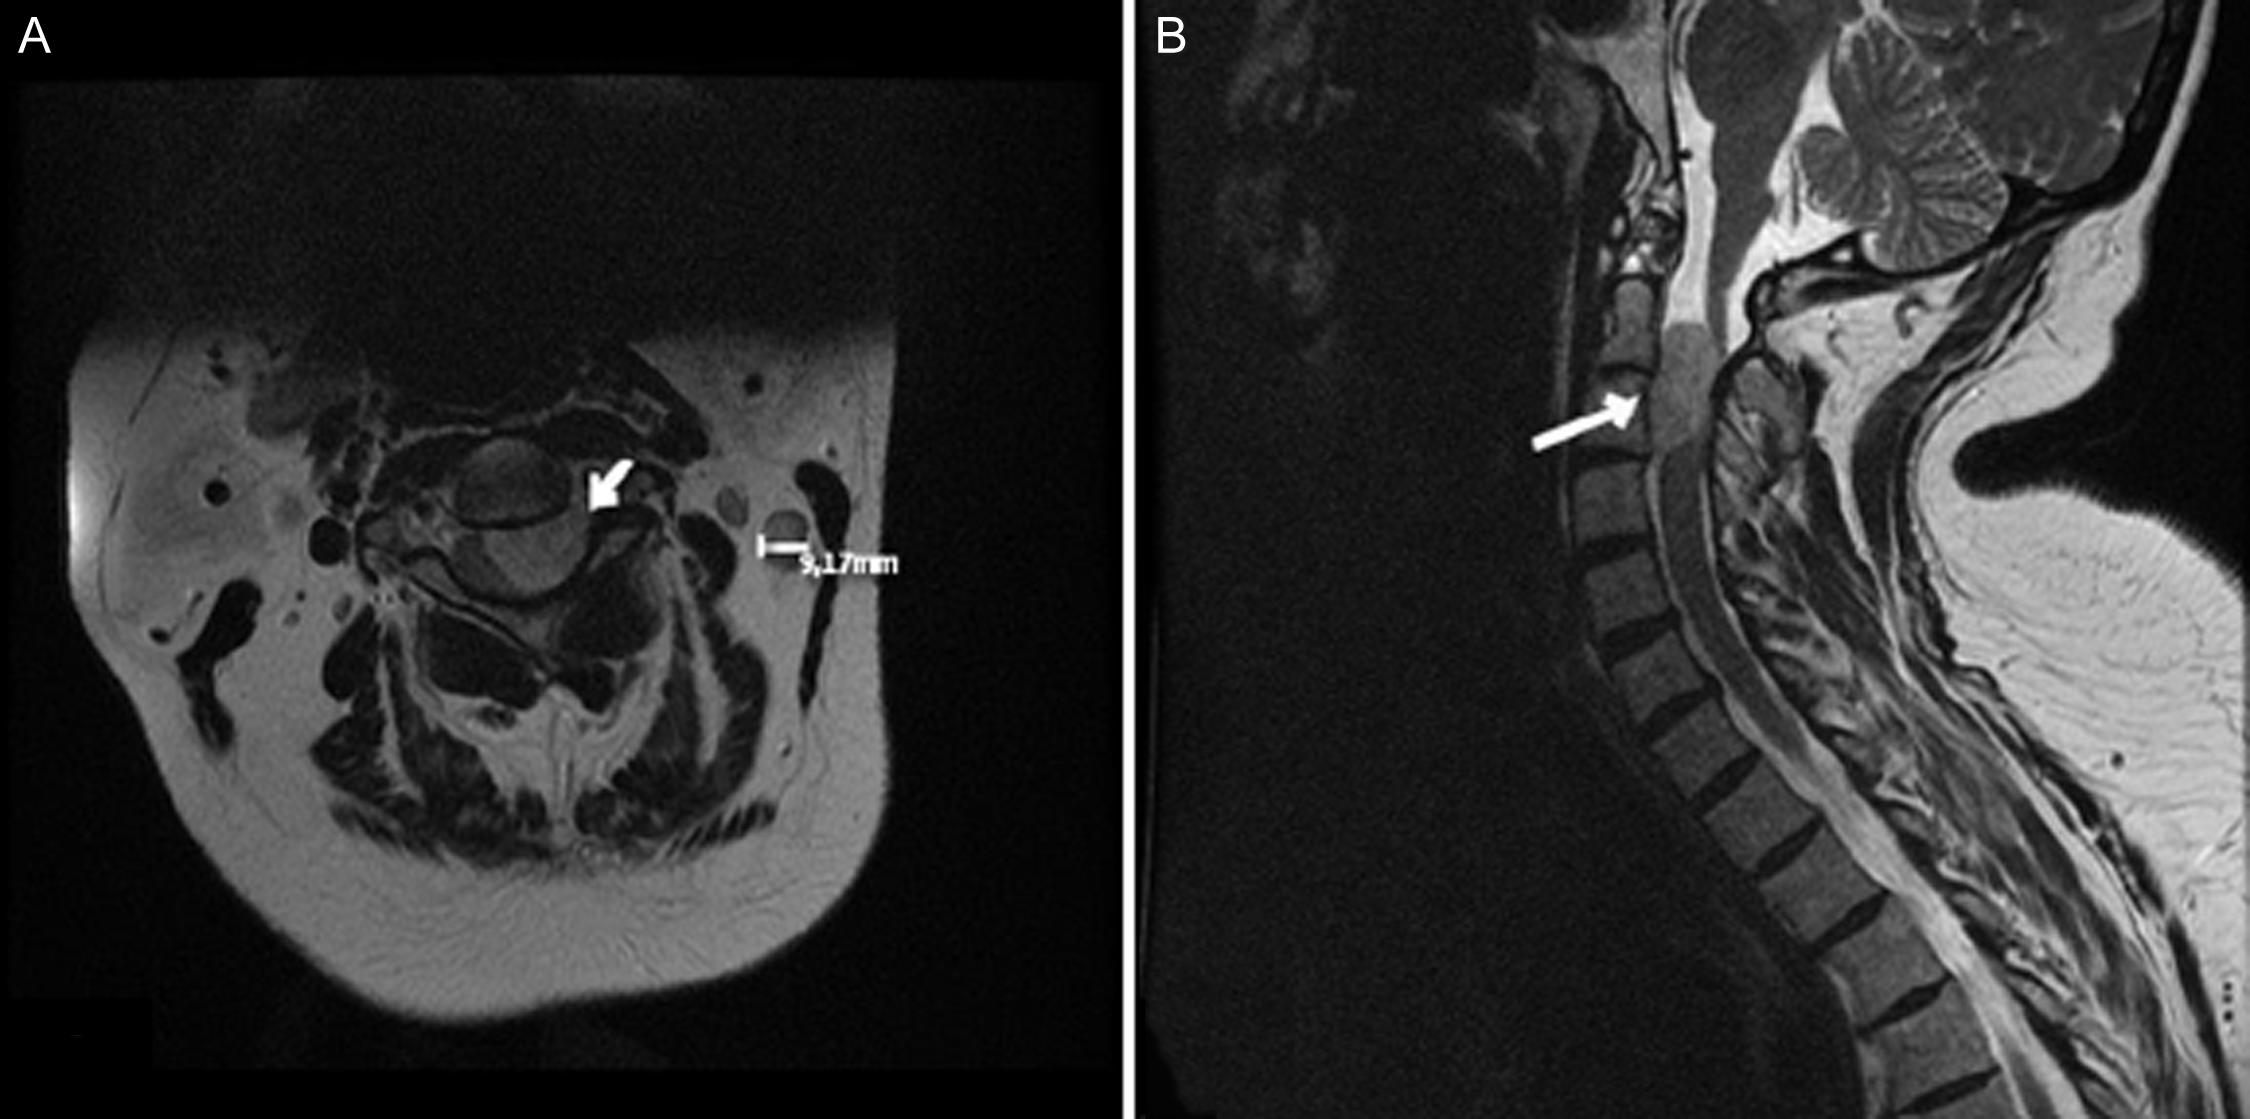

A 56-year-old female presented to our department with left upper extremity neuropathic pain accompanied by left-sided weakness (Table 3). Imaging revealed C2 – C3 lesion with a craniocaudal diameter of 2.9 cm (Figure 2). Intraoperative bony resection, dural opening and tumour exposure are illustrated in Figure 3. Surgery was performed as described in the Methods section. Intraoperative neuromonitoring confirmed proper neurological function. Post-operative imaging confirmed GTR, adequate spinal cord decompression with preserved joint integrity and spinal stability (Figure 4). The patient experienced no surgical complications and was discharged home on post-operative day 2. At 12-month follow-up, no tumour recurrence was reported (Table 4).

Figure 2. Patient 1 preoperative imaging. (A) Axial T2 MRI showing left meningioma (arrow). (B) Sagittal T2 MRI showing spinal cord compression by tumour (arrow). Image obtained with permission from the patient.